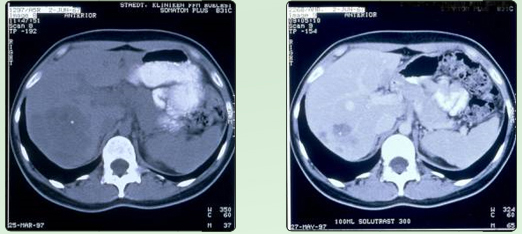

Lebermetastasen vor RTH - Lebermetastasen nach RTH

Lebermetastasen bei Mamma C A |

progrediente Lebermetastasen bei metastasierenden Mamma-CA ( ED.1/96 ) unter systemischer Chemotherapie (4xEC). Nach 6 maliger 1 stündiger regionaler Tiefenhyperthermie unter Beibehaltung der Chemotherapie wurde eine 80%ige Partialremission (Teilrückbildung) erreicht; aus |

Mastall H. Zeit- und situatiosgerechte Einsatzmodelle für komplementäre Verfahren während |

konventionell-onkologischer Therapien: |

32. Medizinische Woche Baden-Baden 1998; 02.XI |